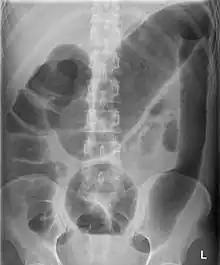

| Toxic megacolon associated with ulcerative colitis. | |

Toxic megacolon is mainly seen in ulcerative colitis and pseudomembranous colitis, two chronic inflammations of the colon (and occasionally, in the other type of inflammatory bowel disease, Crohn's disease). Its mechanism is incompletely understood. It is probably due to excessive production of nitric oxide, at least in ulcerative colitis. The prevalence is about the same for both sexes.